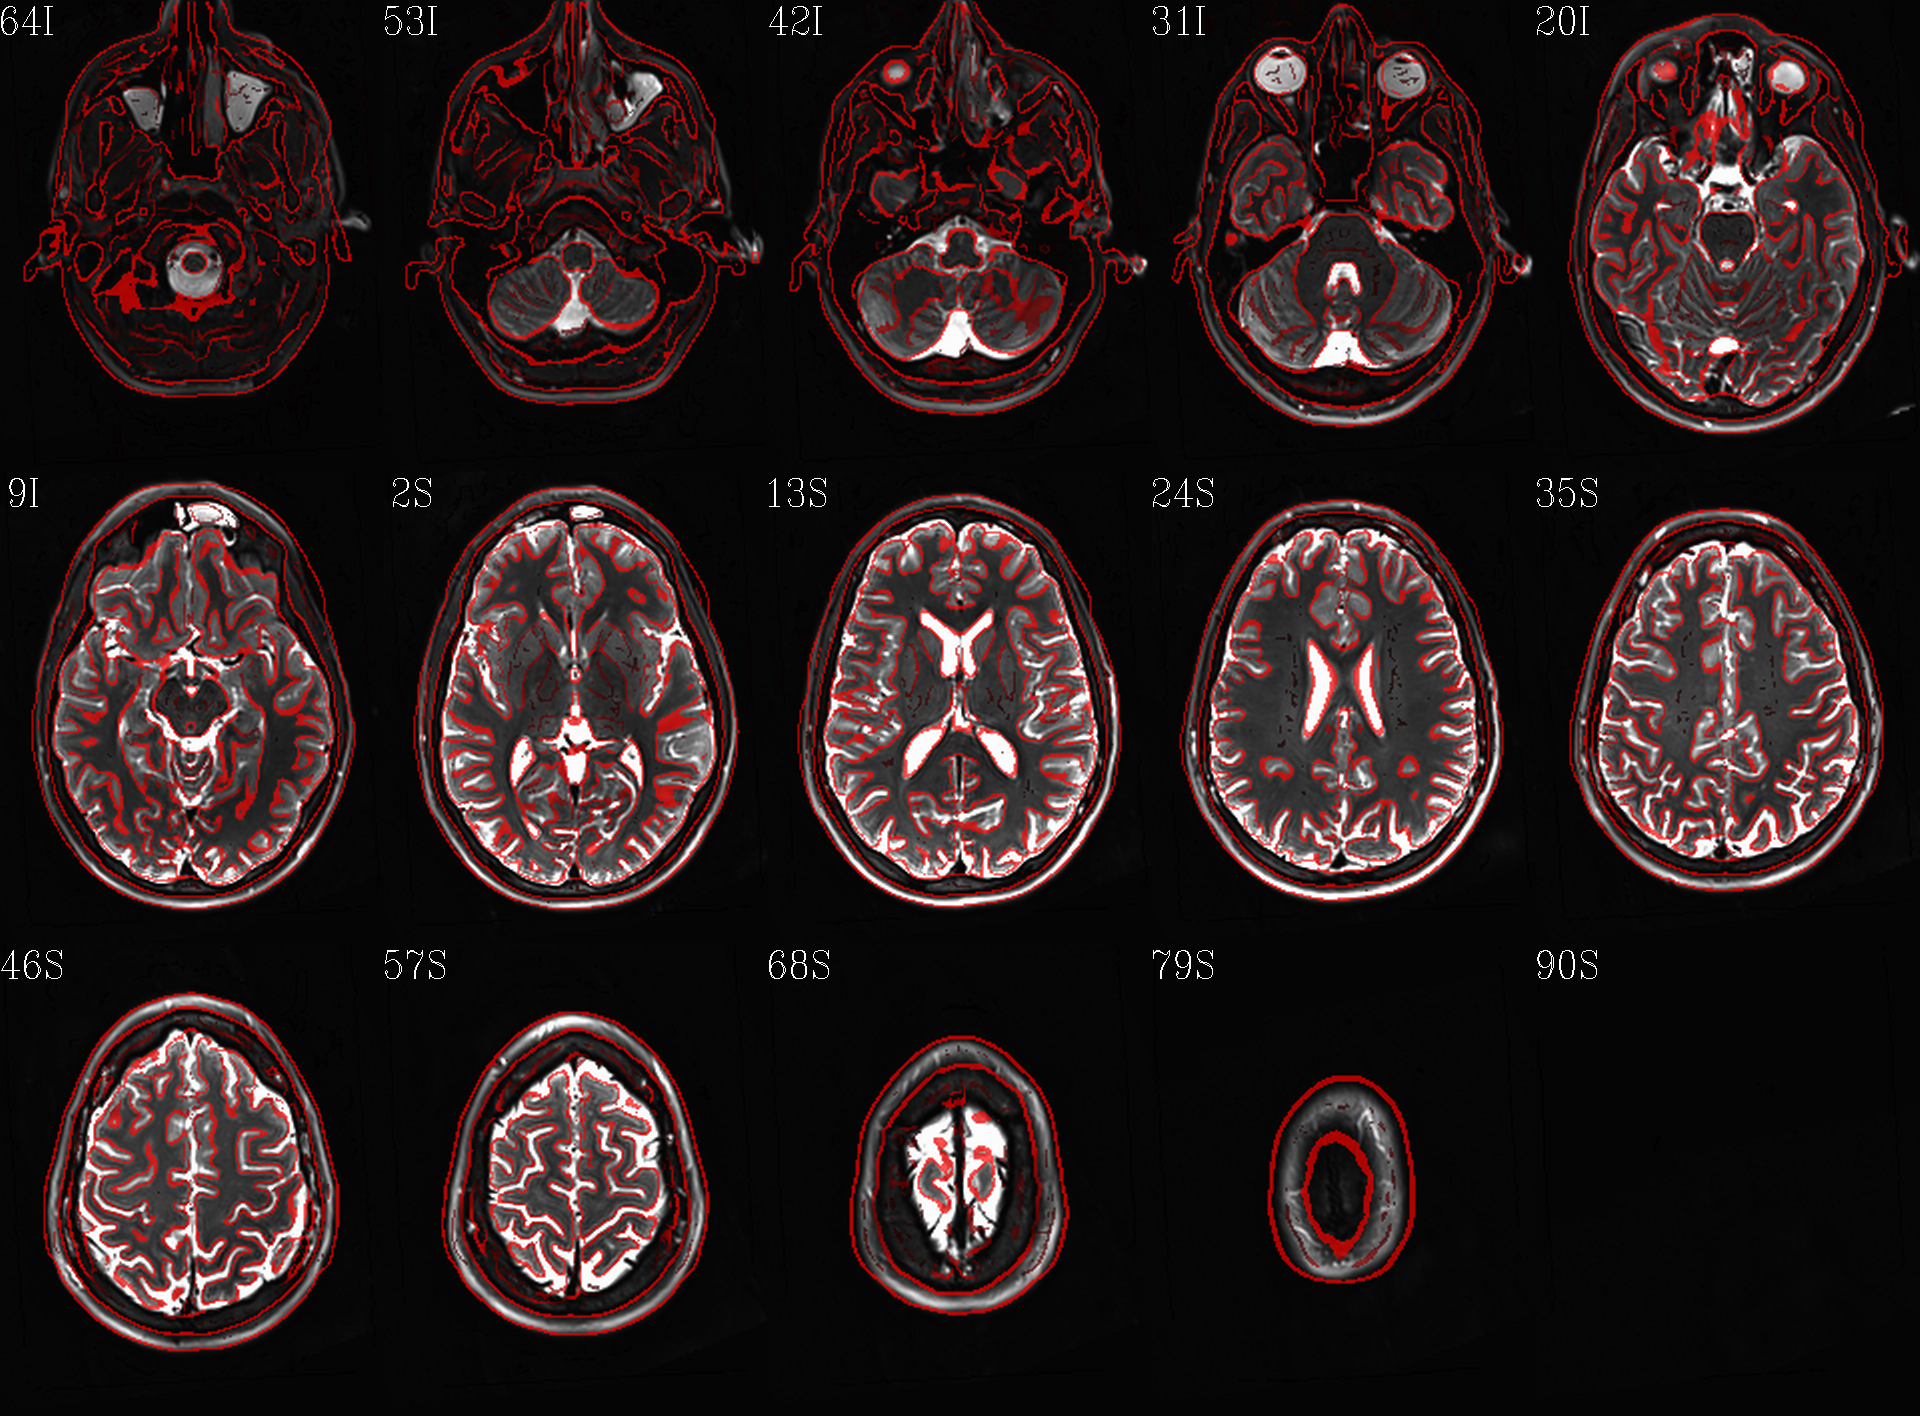

t1w__qc00_t2w_u_et1w.*.png |

autoimages, multiple slices per 3D volume, with single scaling across the volume, showing the T2w reference as the ulay, and an edge-ified version of the T1w volume as the olay, to just the quality of fitting by sulcal features, tissue boundaries, etc. |

t1w__qc01_t2w_u_t1w.*.png |

autoimages, multiple slices per 3D volume; the T2w reference as the ulay, with a translucent version of the T1w volume as the olay. |